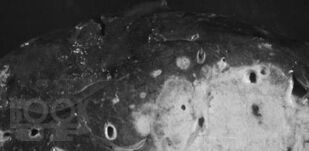

Опухоли гепатопанкреатодуоденальной зоны

Учебное пособие посвящено хирургическим опухолям гепатопанкреатодуоденальной зоны. Освещены вопросы анатомии, физиологии гепатопанкреатодуоденальной зоны, классификация опухолей, методы диагностики и лечения, возможные послеоперационные осложнения.